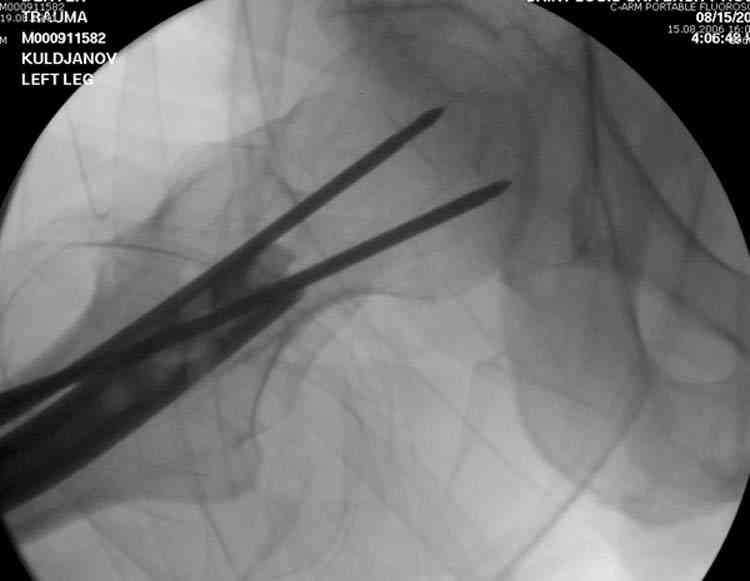

В операционной спереди гвоздя провел два 6.5 мм каннулированных шурупа, также через проксимальное отверстие антеградного гвоздя удалось провести шуруп.

Здесь представлены снимки больного 65 лет, поступившего с диагнозом перелом

бедра после автоаварии.

В первый же день произведено антеградное штифтованием DePuy Trochanteric Nail.

На второй день (7) обнаружен пропущенный перелом,

сделаны Компьютерная Томограмма

и проведены шурурпы через и спереди штифта без удаления.